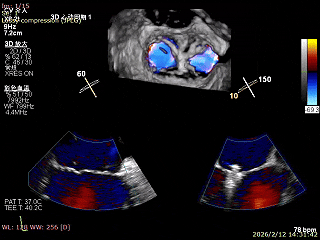

手术效果评估

反流评估:术前4+下降至1+

术前中央反流

术后中央反流

后复查经胸心脏超声,示肺静脉、肝静脉逆流消失,二尖瓣及三尖瓣反流降低至轻度,手术效果良好。